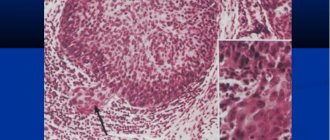

Histology. When removing xanthelasma, it is recommended to take a histological analysis to identify pathological changes.

- Histological studies.

Differential diagnosis is carried out to distinguish the growth from a tumor of the appendageal region. It is important to exclude malignancy by taking a piece of tissue for biomicroscopic examination.

In doubtful cases, a histological examination of tissue obtained from these formations is prescribed. In this case, vacuolated or foamy macrophages are determined - cells that have absorbed fat, which dissolved during processing of the biopsy sample.

Eruptive foci may contain inflammatory infiltrates; verrucous, tendinous and tuberous - connective tissue.